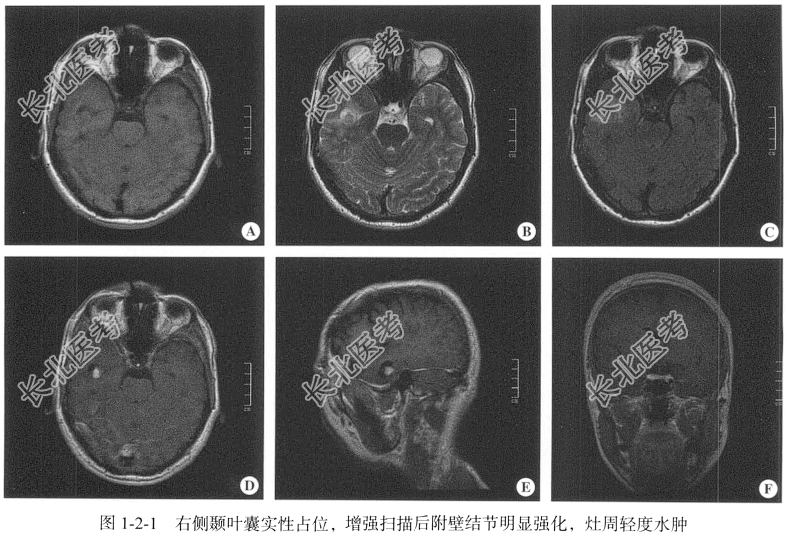

【影像图片】见图1-2-1。

【手术所见】显微镜下见右侧颞叶皮质颜色为淡黄色,术中采用皮质电极在皮质周边进行监测,确定放电范围在颜色异常皮质周边后将皮质切除,切除深度约4.00cm,大小约4.00cm×4.00cm×4.00cm。

【病理所见】肉眼所见:右侧颞叶不整组织1块,体积约1.50cm×1.00cm×1.00cm,切面淡粉色,质地中等;镜下示细胞呈多形性,可见致密网状纤维形成的网络,细胞内含脂质,呈泡沫状,体积较大,多核(图1-2-2);免疫组化结果:GFAP(部分+),Ki-67(3%+),Nestin(+),Neu-N(-),S-100(部分+),IDH-1(散在+),Olig-2(部分+),ATRX(+),Vim(+)。

【病理诊断】结合形态学及免疫组化结果可诊断为多形性黄色星形细胞瘤,WHO Ⅱ级。